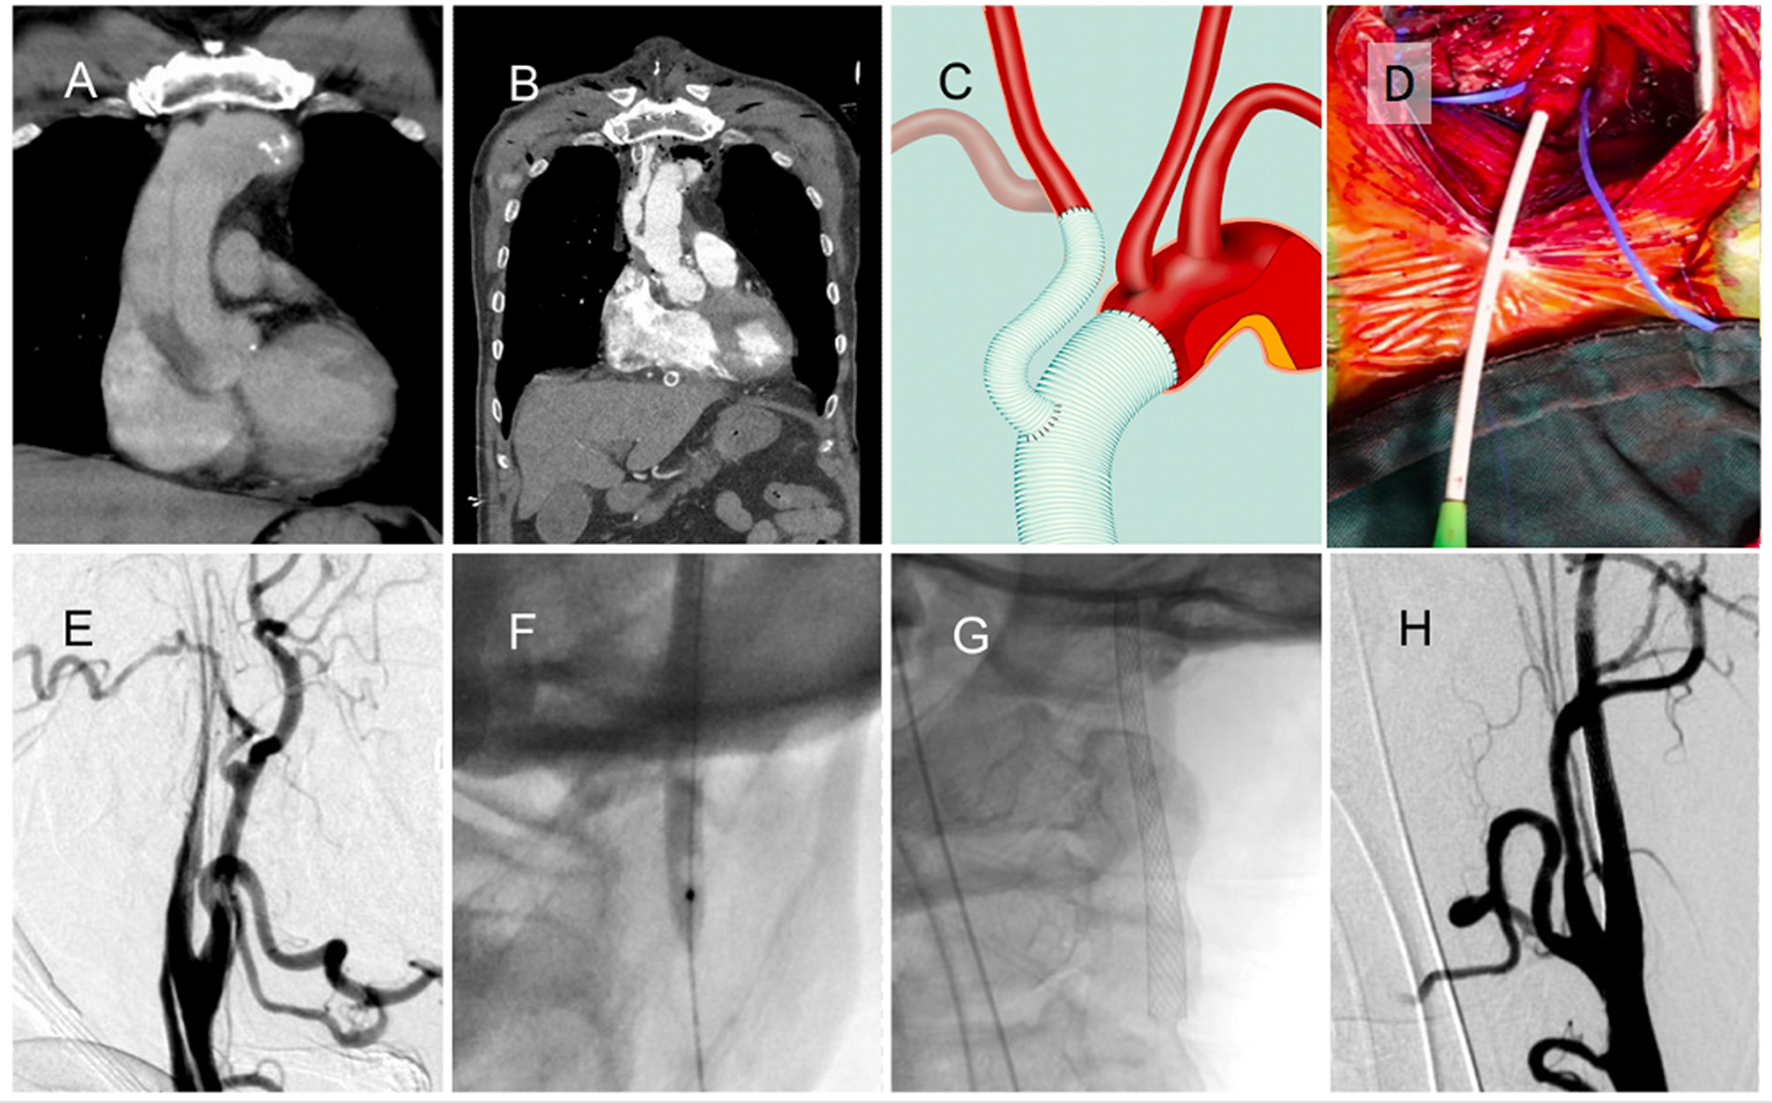

Patient 5. Acute Stroke Immediately After Type A Dissection Operation

A man in his 60s presented with sudden onset chest pain due to type A aortic dissection (Figure 2A). He underwent emergency ascending aortic arch replacement with graft, the innominate artery was debranched, and the innominate artery was reimplanted to the graft (Figures 2B,C). In the intensive care unit (ICU), he experienced seizures and left hemiplegia. The NIHSS score was 29, and the CTA revealed right ICA total occlusion. Carotid exploration was performed from the right neck (Figure 2D), and angiography revealed right ICA dissection and near-complete occlusion with string sign (Figure 2E). Balloon angioplasty (Figure 2F) and carotid stent deployment (Figure 2G) were applied. Complete recanalization was achieved within 1 h (Figure 2H). The patient regained consciousness and muscle power the next day. His mRS was almost 0, with no recurrence or seizure over the 3-month follow-up.

Figure 2

A patient with acute ischemic stroke after type A aortic dissection surgery. (A) Initial type A dissection before operation. (B) Ascending aortic arch replacement with graft placement, innominate artery debranching, and graft reimplantation. (C) Schematic of heart surgery. (D) Carotid exposure and puncture from the right neck. (E) Internal carotid artery (ICA) dissection and near-complete occlusion with string sign. (F) Balloon angioplasty of the occlusion site. (G) Carotid stent deployment. (H) Complete recanalization of the ICA.